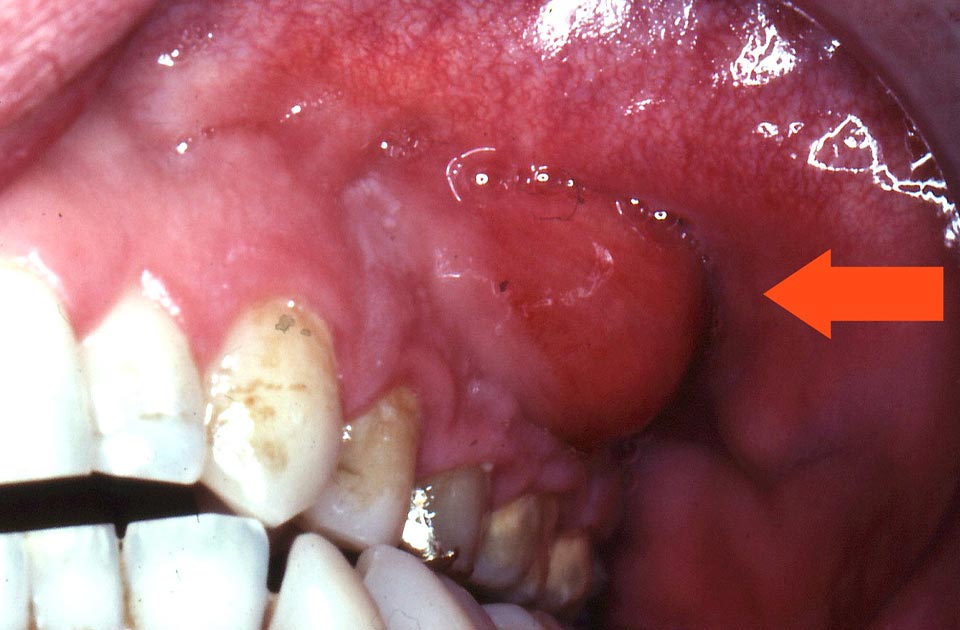

- تورم: تورم در لثه یا صورت در ناحیه دندان عفونی. این تورم ممکن است بهطور ناگهانی ظاهر شود و با افزایش عفونت، شدت آن بیشتر شود.

- ترشح چرکی: ترشح چرکی از لثه یا دندان که نشاندهنده وجود عفونت است. این ترشح میتواند بهصورت مزمن و یا حاد باشد و بهطور معمول با بوی ناخوشایند همراه است.